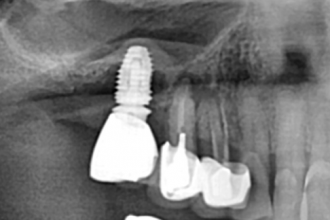

임플란트